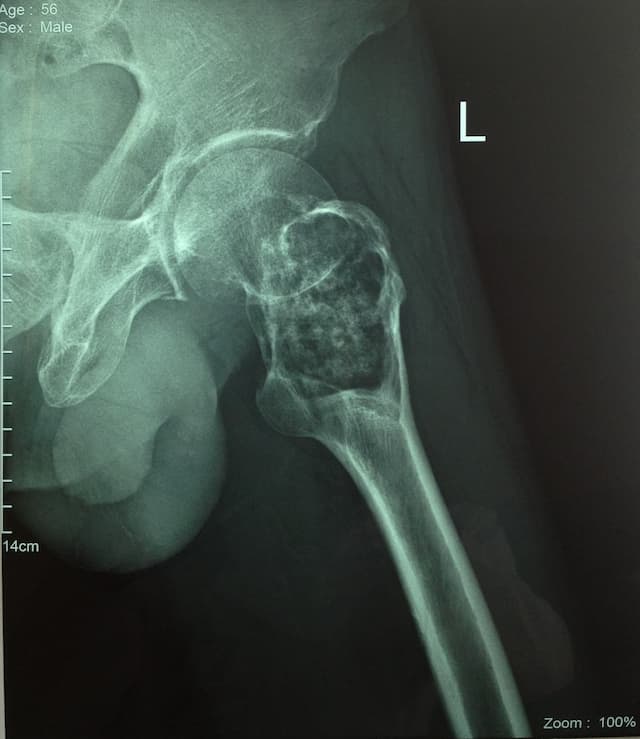

Дунд чөмөгний дээд хэсгийн /проксималь/ хавдар

Дунд чөмөгний проксималь буюу дээд хэсгийг хамарсан яс, зөөлөн эдийн гаралтай хавдрын улмаас түнхний үе, дунд чөмөгний дээд хэсгийг бүхлээр нь солих (мөч хадгалах мэс засал) мэс заслын эмчилгээг хийнэ.

Мэс заслын өмнөх болон дараах рентген зураг